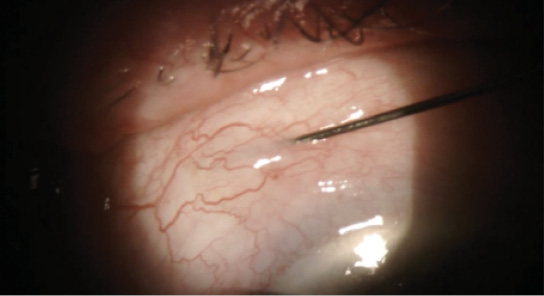

Eyetube | March/April 2019 The Buzz on Eyetube.net Share: View PDF GONIOTOME: AN INTRODUCTION BRIAN A. FRANCIS, MD, MS DEFYING GRAVITY IN CATARACT AND GLAUCOMA SURGERY ARSHAM SHEYBANI, MD AIR/OVD XEN TECHNIQUE IQBAL IKE K. AHMED, MD, FRCSC NEEDLING AT THE SLIT LAMP DAN LINDFIELD, BM FRCOphth Machine Learning and AI in Ophthalmology Ranya Habash, MD arrow-right Created with Sketch. Previous Article